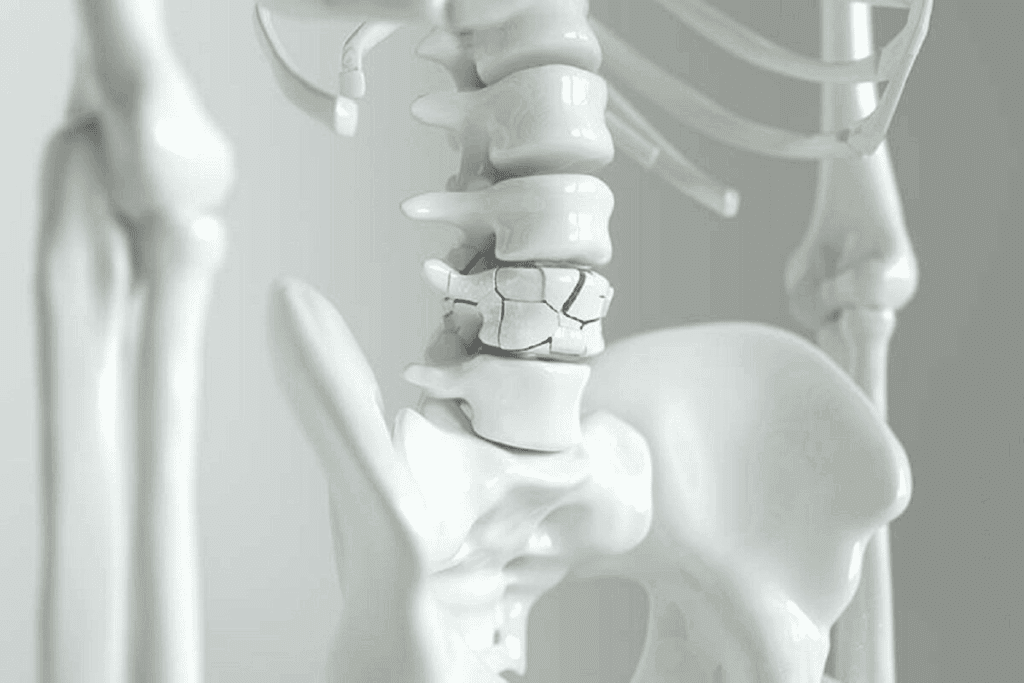

Another example is the intervertebral discs in the spine. These discs act as shock absorbers and let the spine move a little. They help keep the spine flexible and stable.

Symphysial joints can get sick. For example, the pubic symphysis can get osteitis pubis, which causes pain in the groin. Intervertebral discs can also herniate, leading to back pain.